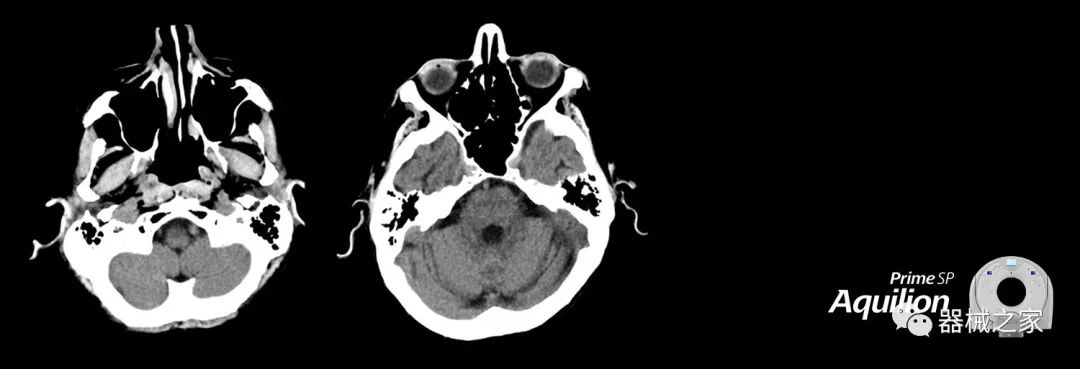

在以患者為中心的放射腫瘤學領(lǐng)域,計算機斷層掃描(CT)的可訪問性,可重復性和靈活性至關(guān)重要。為了建立這些價值,佳能醫(yī)療系統(tǒng)美國公司現(xiàn)在正在擴大其放射腫瘤學CT模擬產(chǎn)品,包括Aquilion Prime SP和Aquilion Lightning 80高級CT系統(tǒng)。除了Aquilion LB之外,Aquilion Prime SP和Aquilion Lightning 80現(xiàn)在還包括放射治療(RT)選項,可為腫瘤學規(guī)劃提供高質(zhì)量的CT成像和精密工具。

Aquilion Prime SP使設(shè)施能夠處理具有挑戰(zhàn)性的案例,同時為員工提供快速,靈活和高效的解決方案。